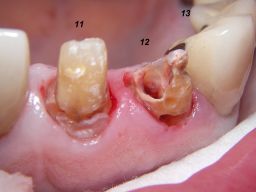

Weil auch die anderen Schneidezahnkronen (12-22) durch Randreparaturen und den schlechten Randschluß erneuerungsbedürftig aussahen, wurden 4 Einzelkronen geplant. Vorher hieß es aber noch, die schlechte Wurzelfüllung im Zahn 12 (Röntgenbild links) besser zu machen. Hierfür wurden am 17.2.06 die alten Kronen 11 und 12 entfernt. Rechts das Bild nach Entfernung von alten Füllungen und Karies. | |